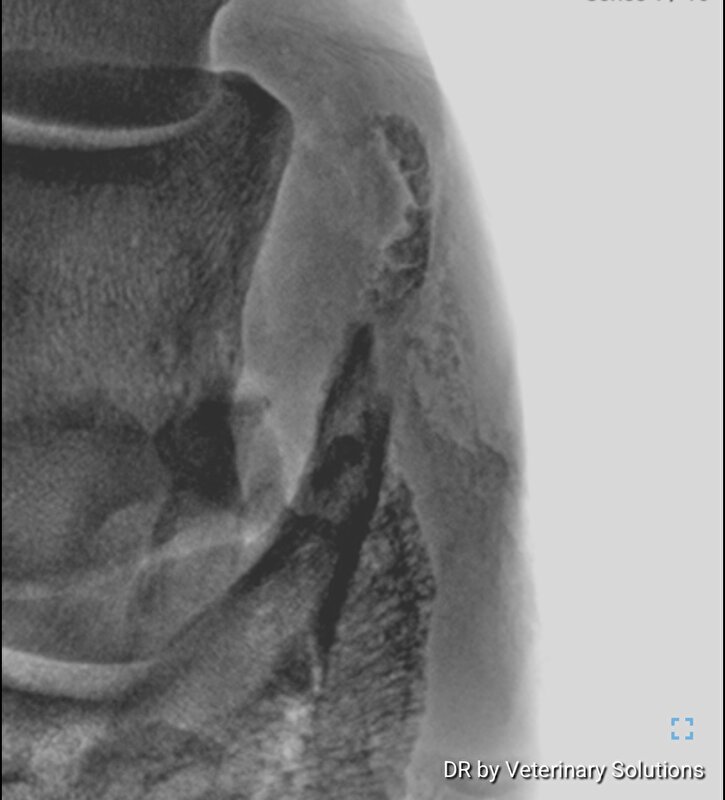

zefiros schreef:Hier best erge verbening vh hoefkraakbeen beide hoeven.